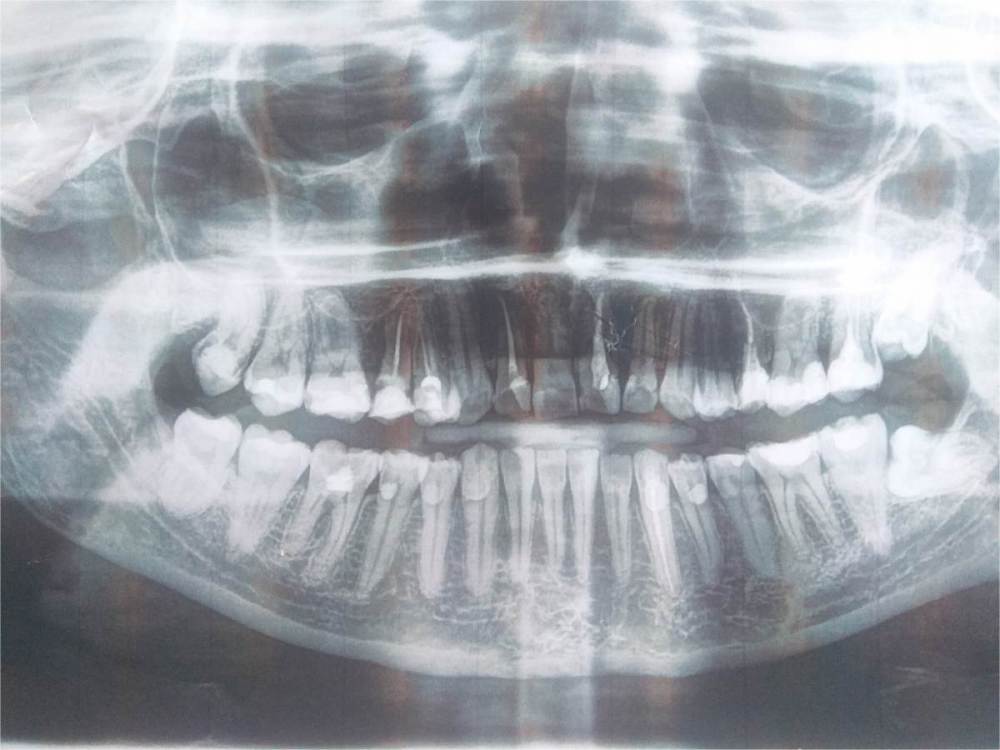

Primavera2023 Опубликовано 28 октября, 2023 Поделиться Опубликовано 28 октября, 2023 (изменено) Здравствуйте. Мой возраст 32 года. 6-8 лет назад мне лечили глубокий кариес сразу на многих зубах. Пломбы стоят близко к нервам. Пару раз стоматолог случайно вскрывал рог пульпы. После лечения была иногда боль на 2-3 дня. Потом всё проходило. Хотелось бы проверить витальность данных зубов на ЭОД. Есть ли смысл? Интересуют следующие зубы : Сверху 1.6. 1.7. 2.6. Снизу: 4.3, 4.4. 4.5. 4.7, 3.4, 3.7 Зуб 1.8. недавно перелечила, глубокий кариес под пломбой, зуб витальный, т.к. была ощутимая боль в процессе. Хочу сделать ЭОД через полгода. Зуб 4.6. резорцин, окрашена только пришеечная часть и корни, что просвечивают под десной. Хочу перелечить, но боюсь потерять зуб! Тоже ради интереса хочу проверить на ЭОД. Зуб 4.8. кариес, 3 дня назад появилось 2 небольших пятна на эмали, стал самопроизвольно поднывать, иду на перепломбировку во вторник. Проверить ЭОД на пульпит? Зуб 3.6. пришлось неделю назад депульпировать, так как развился хронический пульпит. Тут всё понятно. Также на девитальном зубе 1.4. как-то плохо заполнены каналы, или мне так кажется? Ретинированные и дистопированные зубы 2.8, 3.8. планирую удалять. Не беспокоят, но боюсь что разрушат соседние семёрки. Ортопантомограмму делала в июле этого года. Изменено 28 октября, 2023 пользователем Primavera2023 Ссылка на комментарий

Carioznik Опубликовано 29 октября, 2023 Поделиться Опубликовано 29 октября, 2023 (изменено) 28.10.2023 в 12:11, Primavera2023 сказал: Хочу перелечить, но боюсь потерять зуб! 15 зуб -первый кандидат на удаление. На втором и третьем месте :14 и 25. Я бы силы вначале бросил на них. Но все они требуют перелечивания и закрытия коронками. Но С 15 зубом , боюсь что уже поздно что-то делать Ps мнение основано только лишь на этом снимке. Нужен осмотр и возможно 3д снимок Изменено 29 октября, 2023 пользователем Carioznik Ссылка на комментарий